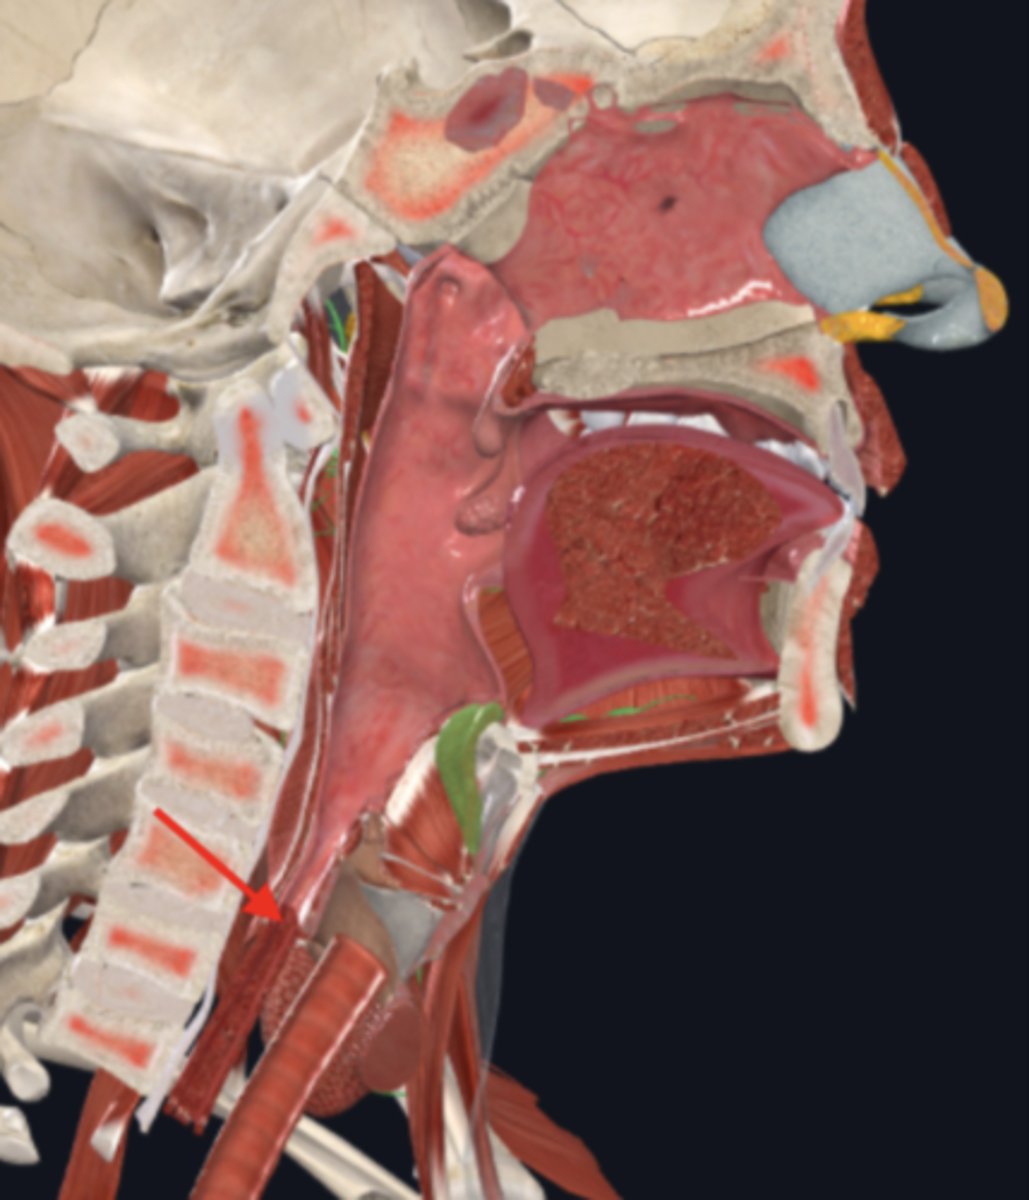

nasopharynx

name the circled region

oropharynx

name the circled region

laryngopharynx

name the circled region

epiglottis

esophagus

upper esophageal sphincter